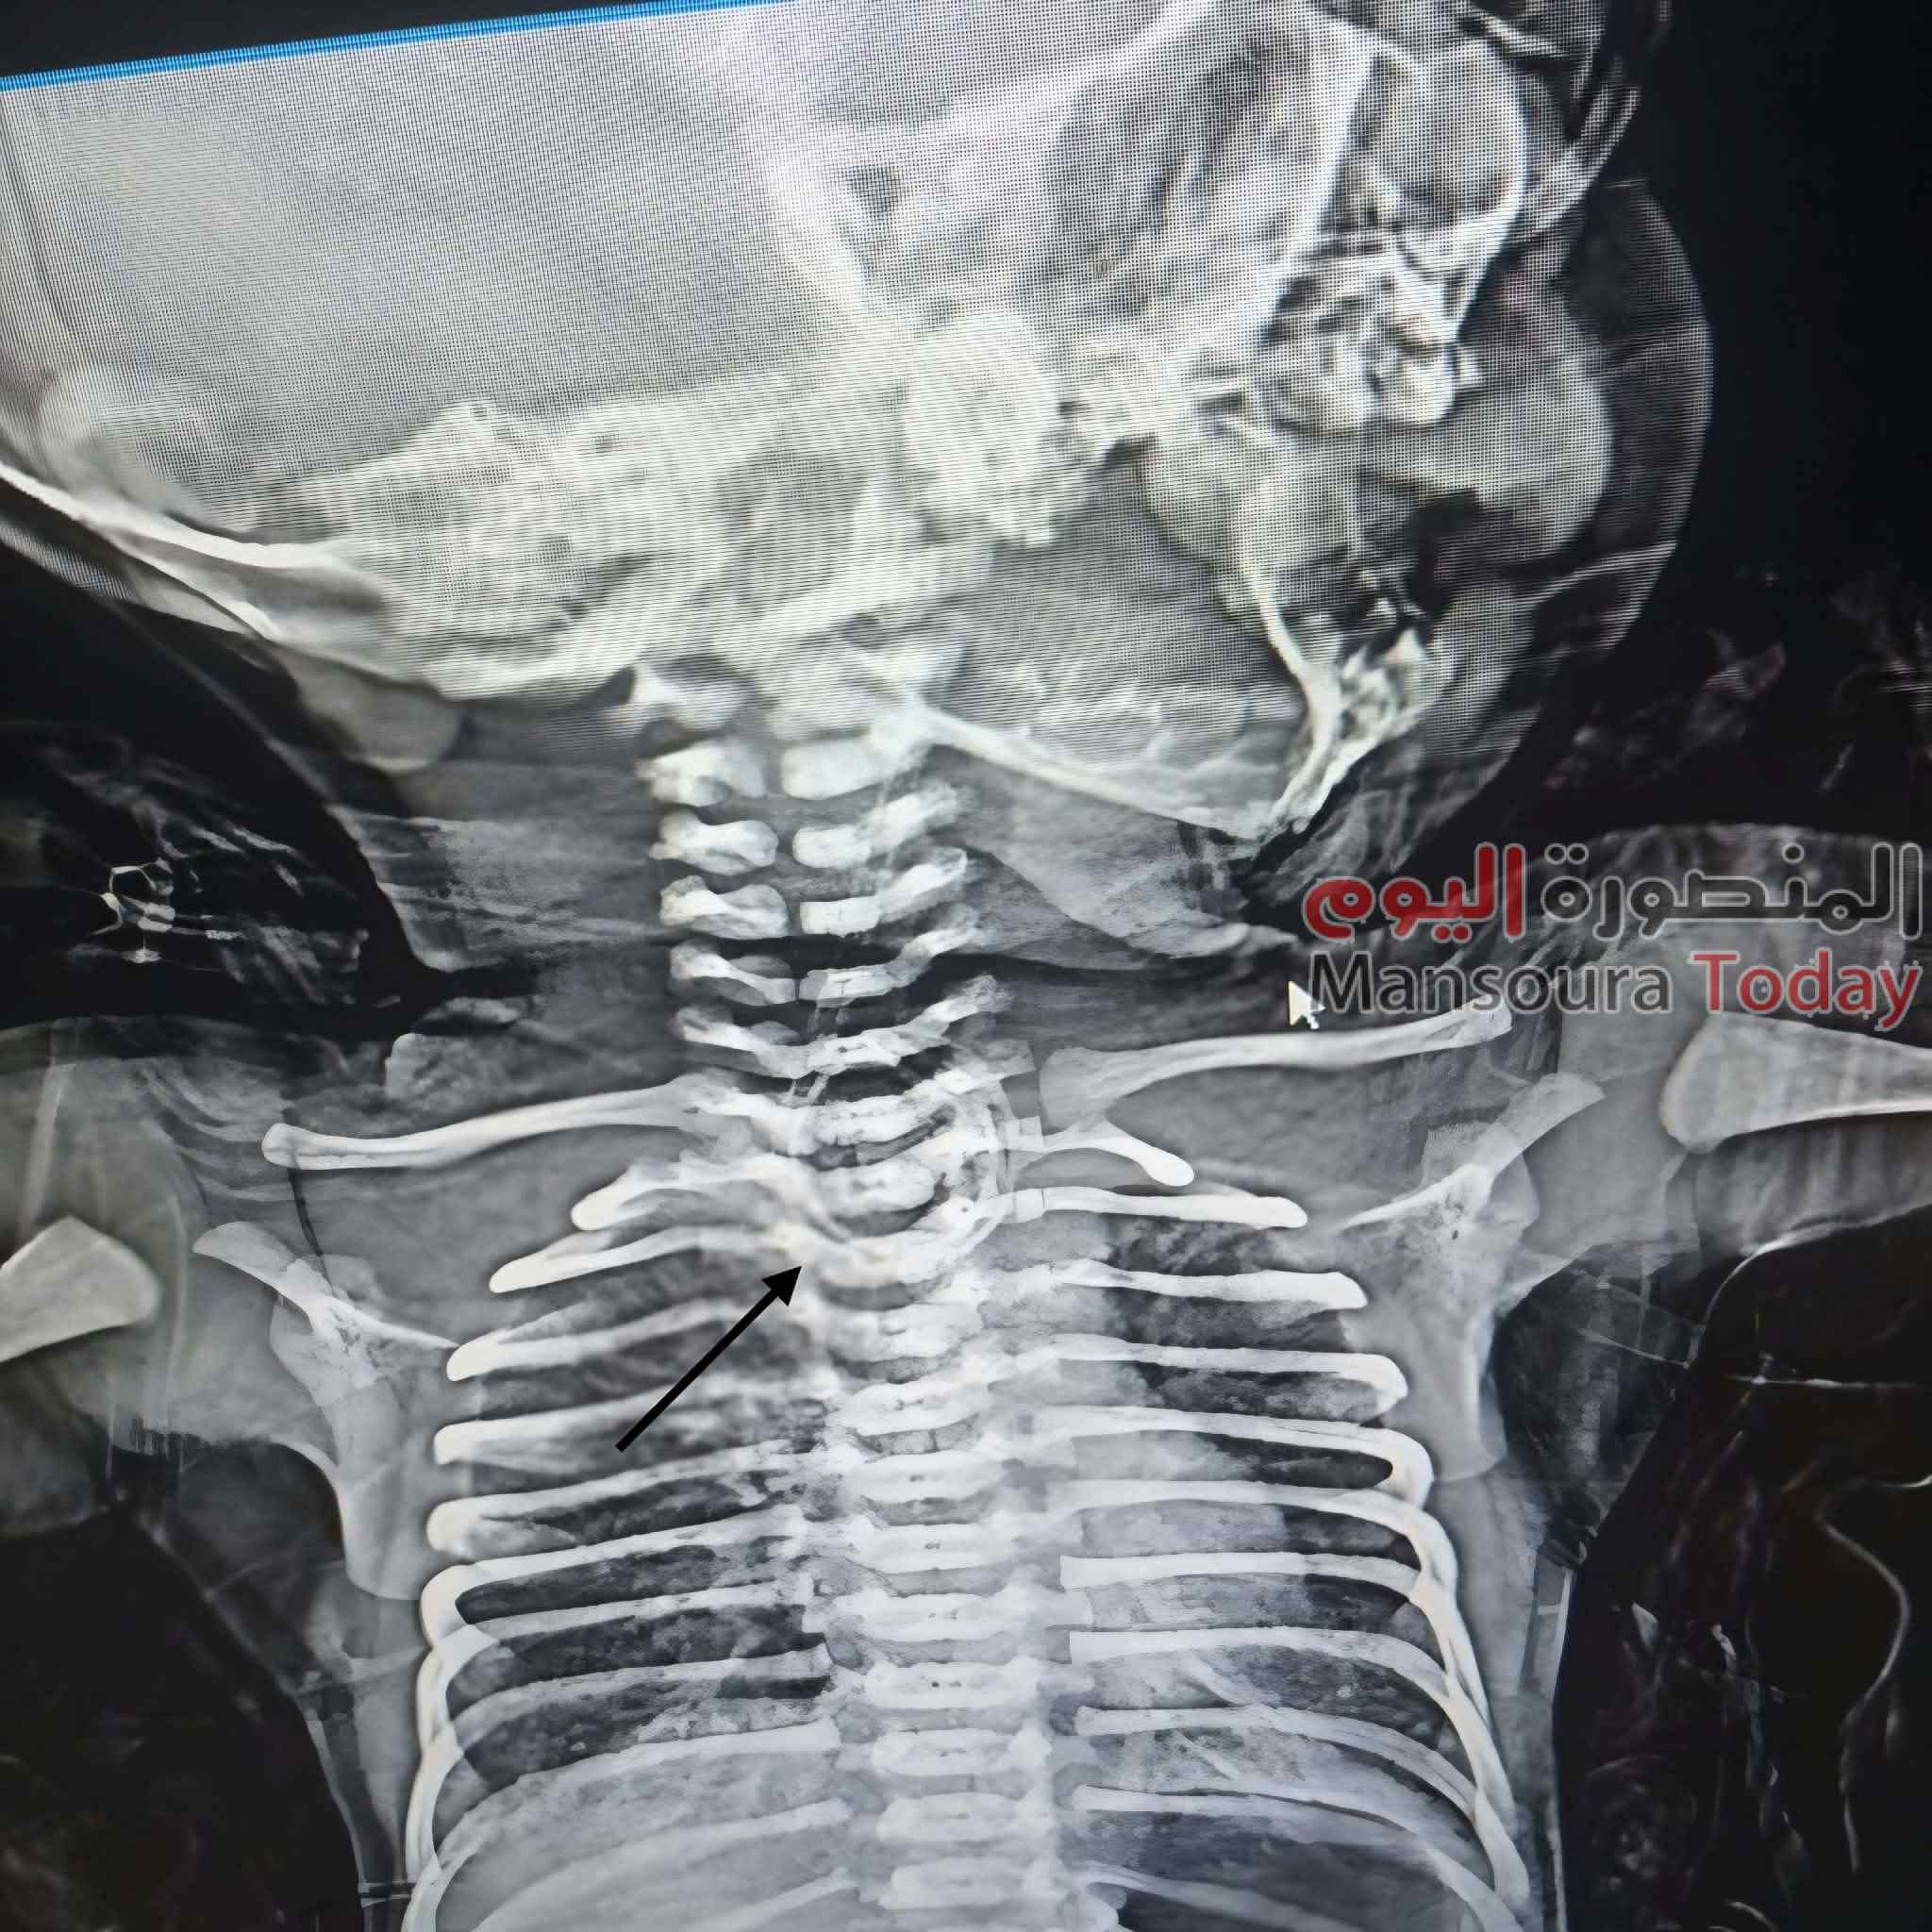

أعلن الأستاذ الدكتور حمودة الجزار، وكيل وزارة الصحة بالدقهلية، نجاح الفريق الطبي بوحدة جراحة الأطفال بمستشفى طلخا المركزي في إجراء جراحة دقيقة و استغرقت قرابه ٣ ساعات لطفل حديث الولادة يبلغ من العمر أسبوعًا، كان يعاني من ناسور خلقي بين المريء والقصبة الهوائية (TEF)، وهو عيب خلقي خطير يتسبب في تسرب الطعام إلى الرئتين ويؤثر على التنفس.

وأكد وكيل الوزارة أن الجراحة تُعد الأولى من نوعها داخل مستشفيات مديرية الصحة بالدقهلية، حيث نجح الفريق الطبي في إصلاح الناسور وتوصيل طرفي المريء رغم وجود مسافة بينهما، وهي من أدق مراحل هذا النوع من الجراحات.